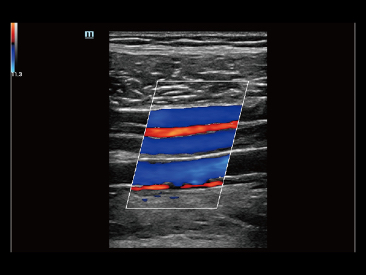

Desde que se fundó la compa?ía, Mindray ha explorado incansablemente nuevas formas de mejorar la confiabilidad del diagnóstico. Con la revolucionaria tecnología de ZONE Sonography?, la nueva plataforma ZST+ de Resona?7 lleva la calidad de la imagen por ecografía a un nivel superior mediante el procesamiento de datos de canal y la adquisición de zona.

Además de la calidad de imagen de primer nivel, Resona?7 también mejora las capacidades de investigación clínica con el revolucionario V?Flow para la evaluación hemodinámica vascular y con la adquisición de planos más inteligente a partir de conjuntos de datos 3D para el diagnóstico del SNC fetal. Al combinar el funcionamiento multitáctil basado en gestos más intuitivo y todas las características clínicas esenciales, Resona?7 realmente lidera las novedades en innovación de ecografías.